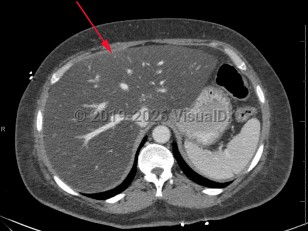

Metabolic dysfunction-associated steatotic liver disease

Screening for MASLD is of the utmost importance in patients with underlying risk factors, primarily obesity and metabolic syndrome, as it is often asymptomatic. American Diabetes Association (ADA) guidelines recommend routine MASLD screening in patients with diabetes and prediabetes. Some patients report vague symptoms such as fatigue or mild right upper quadrant abdominal pain. If MASLD progresses to cirrhosis, patients will often present with signs and symptoms of advanced liver disease: spider angiomata, gynecomastia, ascites, jaundice, and peripheral edema. Cardiovascular disease is the leading cause of death in persons with MASLD.